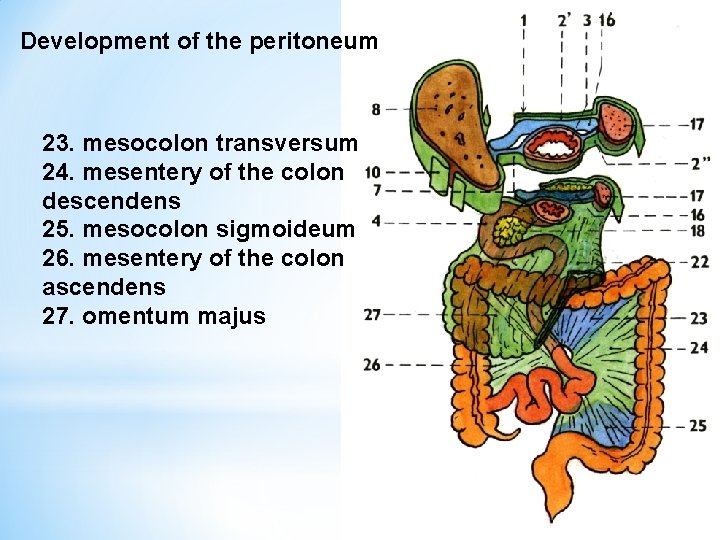

Development of the peritoneum 23. mesocolon transversum 24. mesentery of the colon descendens 25. mesocolon sigmoideum 26. mesentery of the colon ascendens 27. omentum majus